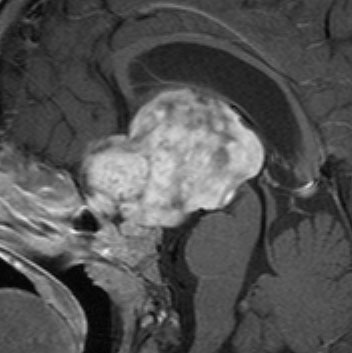

視索に限局する毛様細胞性星細胞腫

左の視索の内部から発生したもので,これも単神経・視神経膠腫と同様によくみるものです。左の画像で視神経交叉が全く侵されていないのがわかります。

単視神経膠腫は全摘出できるのですが,このタイプは外側膝状体へ及ぶので完全摘出ができません。部分摘出と定位放射線治療が適応となります。